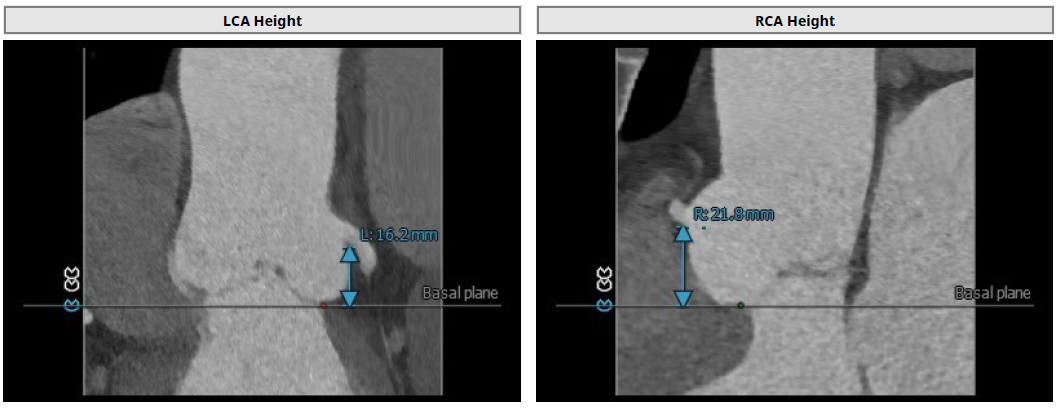

3.患者双侧冠脉开口高度可LCA:16.2mm,RCA:21.8mm;

左冠高度:16.2mm;右冠高度:21.8mm